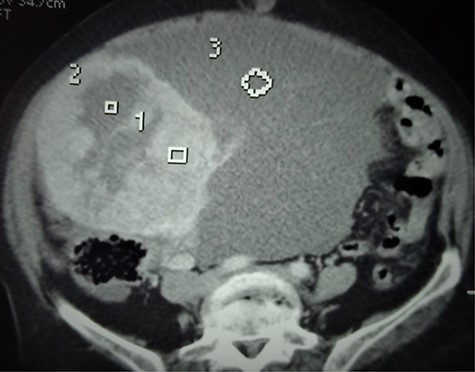

A 68-year-old postmenopausal multiparous (parity 5) patient with a medical history of hypertension was referred to our hospital for pelvic pains and progressively increasing abdominal mass over 3 months. Physical examination revealed a voluminous abdominopelvic mobile mass with dullness in the flanks. A contrast computerized tomography (CT) scan revealed a large right-solid cystic adnexal tumor measuring 120 × 110 mm with peritoneal carcinosis and left inguinal lymph node metastasis (Fig. 3).

Axial CT scan showing the bulky abdominopelvic mass (3) with solid and cystic components (1 and 2, respectively).